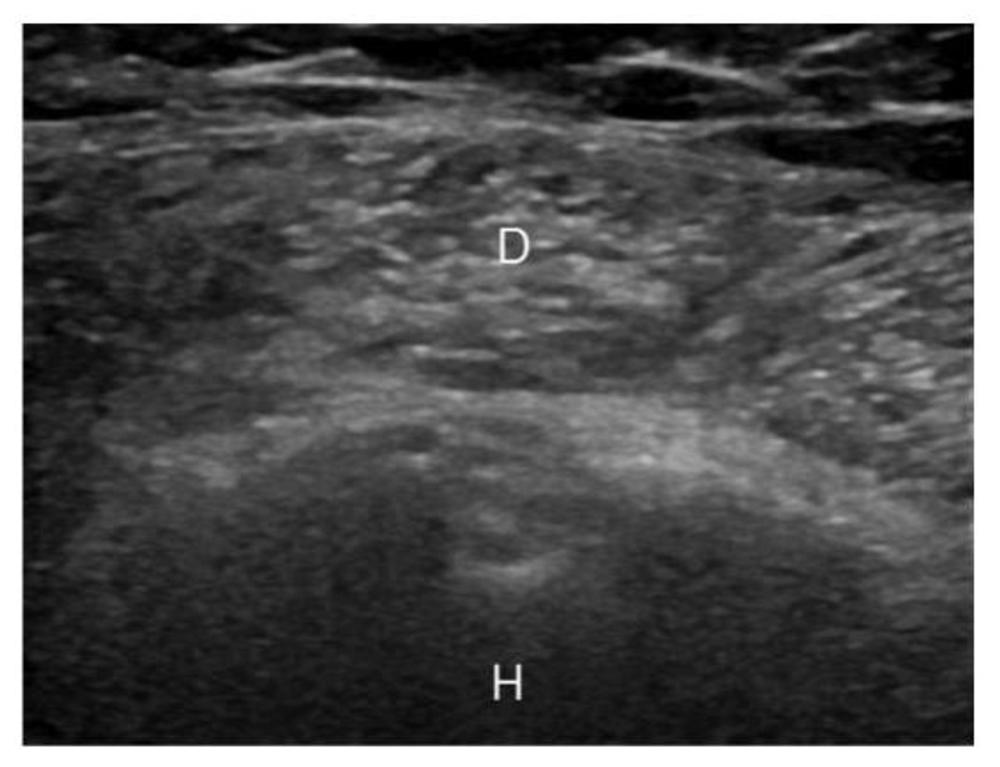

A shoulder muscle that appears unusually bright on ultrasound (US) may be a warning sign of diabetes, according to a study being presented at RSNA 2018.

More than 10 years ago, musculoskeletal radiologist Steven B. Soliman, DO, from Henry Ford Hospital in Detroit, began noticing a pattern when images of the deltoid muscle appeared bright on US.

The US examinations were blindly reviewed by two musculoskeletal radiologists who were asked to classify the patients, based on the brightness of their shoulder muscle, into one of three categories: normal, suspected diabetes and definite diabetes. A third musculoskeletal radiologist acted as an arbitrator in the cases where the other two radiologists disagreed.

A hyperechoic deltoid muscle was also a strong predictor of pre-diabetes. The musculoskeletal radiologists assigned all 13 pre-diabetic US examinations to either the “suspected diabetes” or “definite diabetes” categories.

The reasons for the brighter-appearing shoulder muscle on US among patients with diabetes is not completely understood, according to Dr. Soliman, but the researchers suspect it is due to low levels of glycogen in the muscle. A study of muscle biopsies in patients with diabetes found that muscle glycogen levels are decreased up to 65 percent. Prior research has also shown that the muscles of athletes appear brighter on US after exercise, when their glycogen stores are depleted.